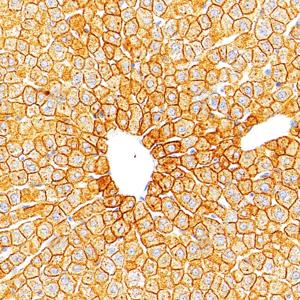

IHC检测Cytokeratin 18蛋白(货号 GB15232). 样品: 小鼠肝, 4%多聚甲醛 (货号G1101) 固定12-24小时. 抗原修复: 柠檬酸抗原修复液(干粉, pH 6.0) (G1201), 高压锅均匀喷气计时2分钟. —抗: 1: 500稀释, 4℃ 孵育过夜. 二抗: S-vision免疫组化多聚二抗(山羊抗小鼠), 即用型(货号G1301), 室温孵育20分钟. |